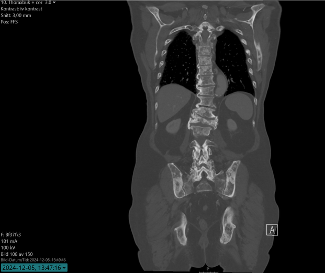

Efter ytterligare 4 månader görs en DT torax/buk på grund av nytillkommen smärta I bröst- och ländrygg. Svaret visar inga viscerala metastaser.

Efter 6 månaders behandling görs en DT där status bedöms som väsentligen oförändrat. Fortsatt utbredd metastasering till skelett utan säker progress. Inga nytillkomna destruktioner. Inget nytillkommet i lungor eller pleura, inga patologiskt förstorade lymfkörtlar. Inget nytillkommet i buken.